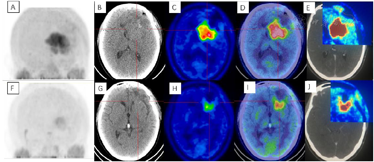

术后3周患者就诊于头颈肿瘤放化疗科,专科查体:左眼睑下垂,神清,言语清晰,伸舌居中,双侧瞳孔等大等圆,对光反射存在,四肢感觉活动可,肌力肌张力正常。2017年7月MR(图4)示左额叶术后改变伴出血,病灶内侧部分考虑肿瘤残留可能。为了更好地评估术后残留病变范围和制定放疗计划,患者行11C-MET PET/CT检查(图5A-D),结果示左侧脑室前角旁-左侧基底节区团块状稍高密度影,蛋氨酸代谢异常增高,考虑肿瘤残留。参照2016 ESTRO-ACROP指南[1],继发性胶质母细胞瘤放疗GTV靶区需包含术腔、T1增强上的强化区域及T2 FLAIR上的高信号区域,术后PET/CT显像所示的氨基酸代谢活跃病灶被包含在GTV之内(图5E)。患者于2017年7月始行左额叶病灶放疗(PTV 60Gy/30F,同步口服替莫唑胺化疗75mg/m2,qd)。结束后复查PET/CT(图5F-I)示病变范围明显缩小,代谢程度较前减低,左额叶少许病变存活,遂对残留病灶局部放疗加量(GTV如图5J,6Gy/3F)。放疗过程顺利,期间出现Ⅲ°白细胞减低,予以升白细胞治疗后好转出院。后于2017年10月起口服替莫唑胺辅助化疗(150~200mg/m2,d1-d5,q28d),期间规律复查。

2018年3月、6月MR复查发现病灶范围逐渐增大(图6),提示不除外复发可能。患者除了轻微头痛之外并无明显不适,临床考虑假性进展,予安维汀100mg治疗后症状好转。2018年8月复查11C-MET PET/MR显像未见明显代谢增高病灶,证实为假性进展(图7)。2018年11月复查未见明显肿瘤复发,2019年3月2日MRI复查(图8)再次提示病变增大,考虑肿瘤进展。2019年3月行PD-1单抗(拓益)治疗,治疗过程中患者出现行走不稳,1月后患者不慎跌倒,外院就诊行颅脑CT未见明显出血。期间发现患者肝功能异常,给予护肝治疗后好转。2019年5月复查PET/MR(图9)提示左侧额叶前下部、左侧海马区及左侧颞叶前部蛋氨酸代谢较前次增高,其中左侧海马及左额叶直回ASL灌注相对增高,考虑复发可能,免疫治疗后存活。遂停用免疫治疗,根据患者全基因组测序结果选择靶向药物安罗替尼治疗(主要针对VEGFR、PDGFR、FGFR、c-KIT多个靶点),2019年12月复查PET/MR(图10)提示病变活性受抑。电话随访得知患者因武汉疫情影响无法按期治疗和复查,后合并肺部感染,于2020年8月去世。